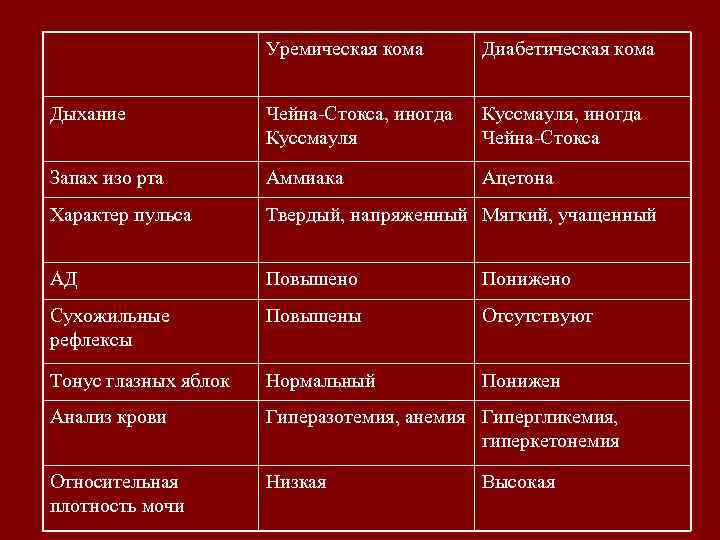

Уремическая кома Диабетическая кома Дыхание Чейна-Стокса, иногда Куссмауля, иногда Чейна-Стокса Запах изо рта Аммиака Ацетона Характер пульса Твердый, напряженный Мягкий, учащенный АД Повышено Понижено Сухожильные рефлексы Повышены Отсутствуют Тонус глазных яблок Нормальный Понижен Анализ крови Гиперазотемия, анемия Гипергликемия, гиперкетонемия Относительная плотность мочи Низкая Высокая

Уремическая кома Диабетическая кома Дыхание Чейна-Стокса, иногда Куссмауля, иногда Чейна-Стокса Запах изо рта Аммиака Ацетона Характер пульса Твердый, напряженный Мягкий, учащенный АД Повышено Понижено Сухожильные рефлексы Повышены Отсутствуют Тонус глазных яблок Нормальный Понижен Анализ крови Гиперазотемия, анемия Гипергликемия, гиперкетонемия Относительная плотность мочи Низкая Высокая